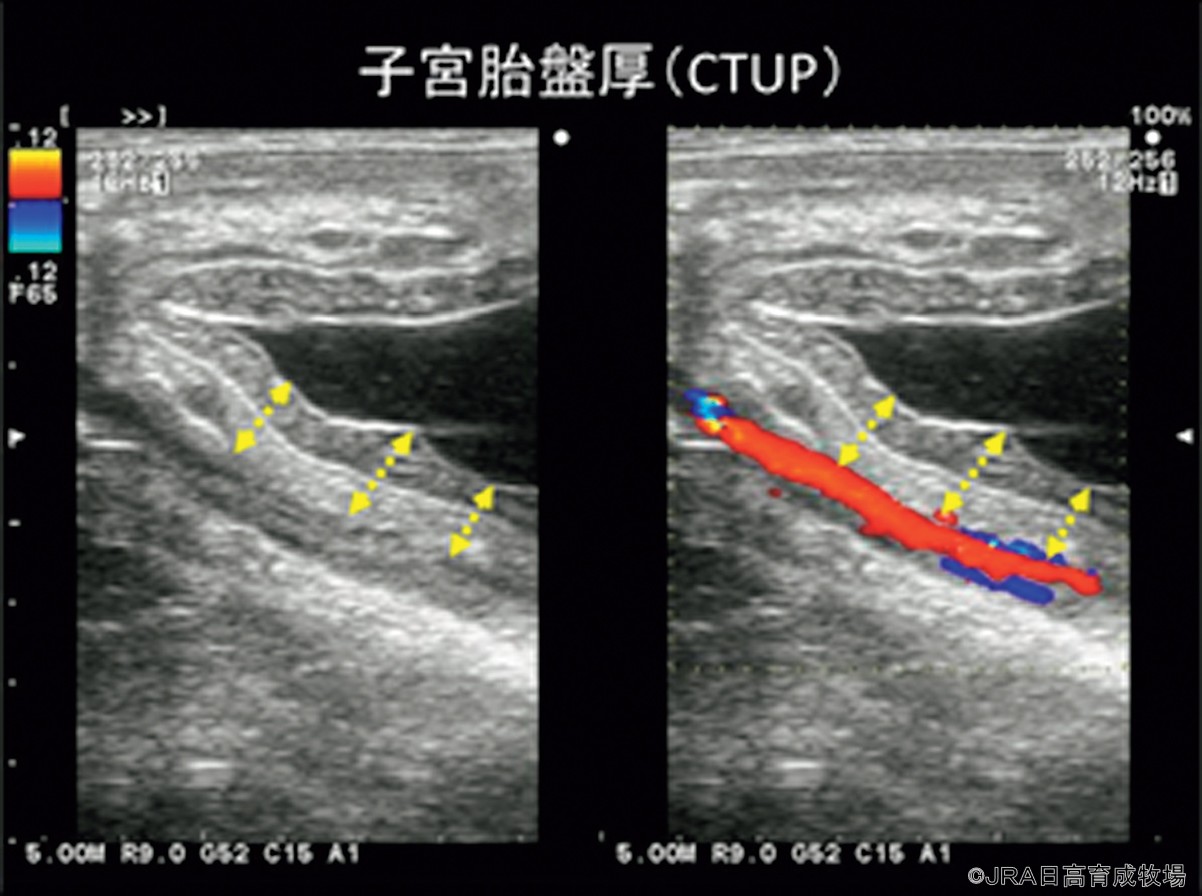

①超音波検査(経直腸、経腹壁):超音波検査で主に見たいものはCTUP(子宮胎盤厚)や胎動、胎子心拍、羊水/尿膜水の性状変化となります。特にCTUPについては経直腸の超音波検査で観察、測定がし易く、重要なポイントとなります(=図参照)。正常妊娠でも妊娠期とともにCTUP値は増加しますが、目安として、270─300日で8ミリ以上、300─330日で10ミリ以上、330日以降で12ミリ以上の場合には胎盤炎によるCTUPの異常な肥厚が考えられます。また厚さだけでなく、辺縁不整や浮腫像を認める場合も胎盤炎を疑います(Kimura, 2018)。また、妊娠期が進むにつれて胎子も大きく重くなり母馬のお腹に沈んでいくため、胎児心拍や羊水/尿膜水の正常変化については5カ月齢ごろから経直腸ではなく経腹壁からアプローチする必要が出てきます。